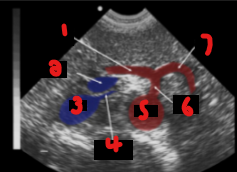

Label the crossed-out structures on this image.

Celiac artery

Liver

SMA

Aorta

Vertebra